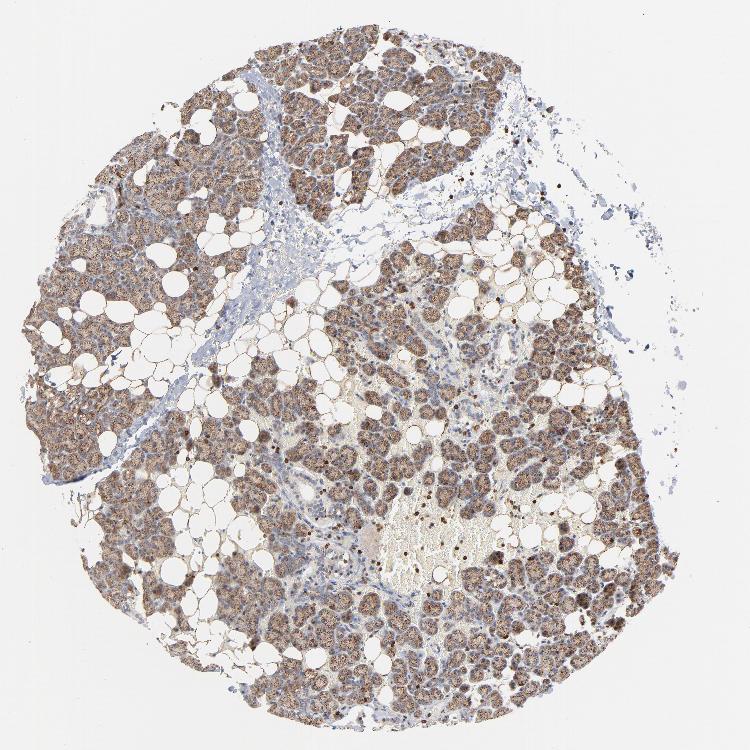

SALIVARY GLAND - Antibody stainingi

Antibody staining in the annotated cell types in the current human tissue is reported as not detected, low, medium, or high, based on conventional immunohistochemistry profiling in selected tissues. This score is based on the combination of the staining intensity and fraction of stained cells.

Each image is clickable and will lead to virtual microscopy that enables deeper exploration of all samples and also displays staining intensity scores, fraction scores and subcellular localization as well as patient and tissue information for each sample.

Antibody HPA003351Antibody HPA003355Antibody CAB021892

Glandular cells LowMediumNot detected